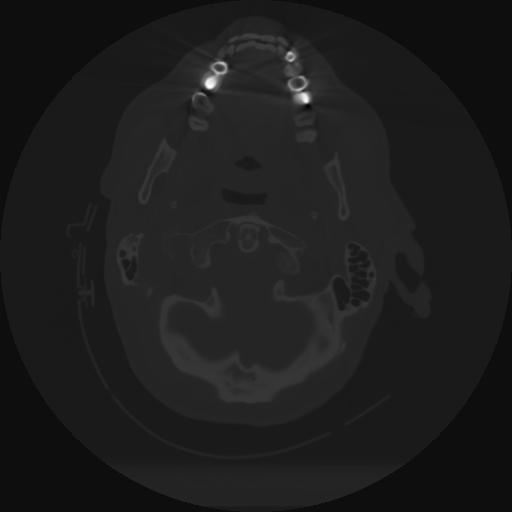

12 P.BLANDAS,,Vol,0.5,P.BLANDAS,,